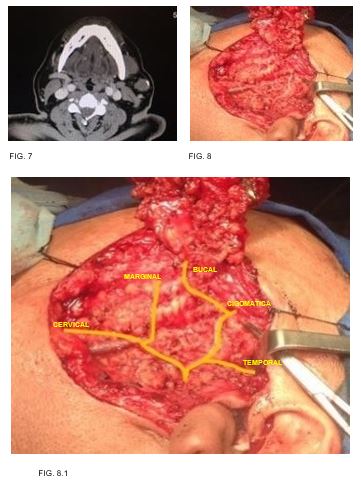

Caso 4: masculino 56 años de edad, antecedente de diabetes mellitus, tabaquismo e hiperplasia prostática, con tumor parotídeo izquierdo de 3cm en su eje mayor, resultando en adenoma pleomorfo. (FIG. 7-8)

5

Referencias anatómicas más importantes para identificación de tronco principal de nervio facial en su salida por agujero estilomastoídeo (FIG. 21):

12

13

14